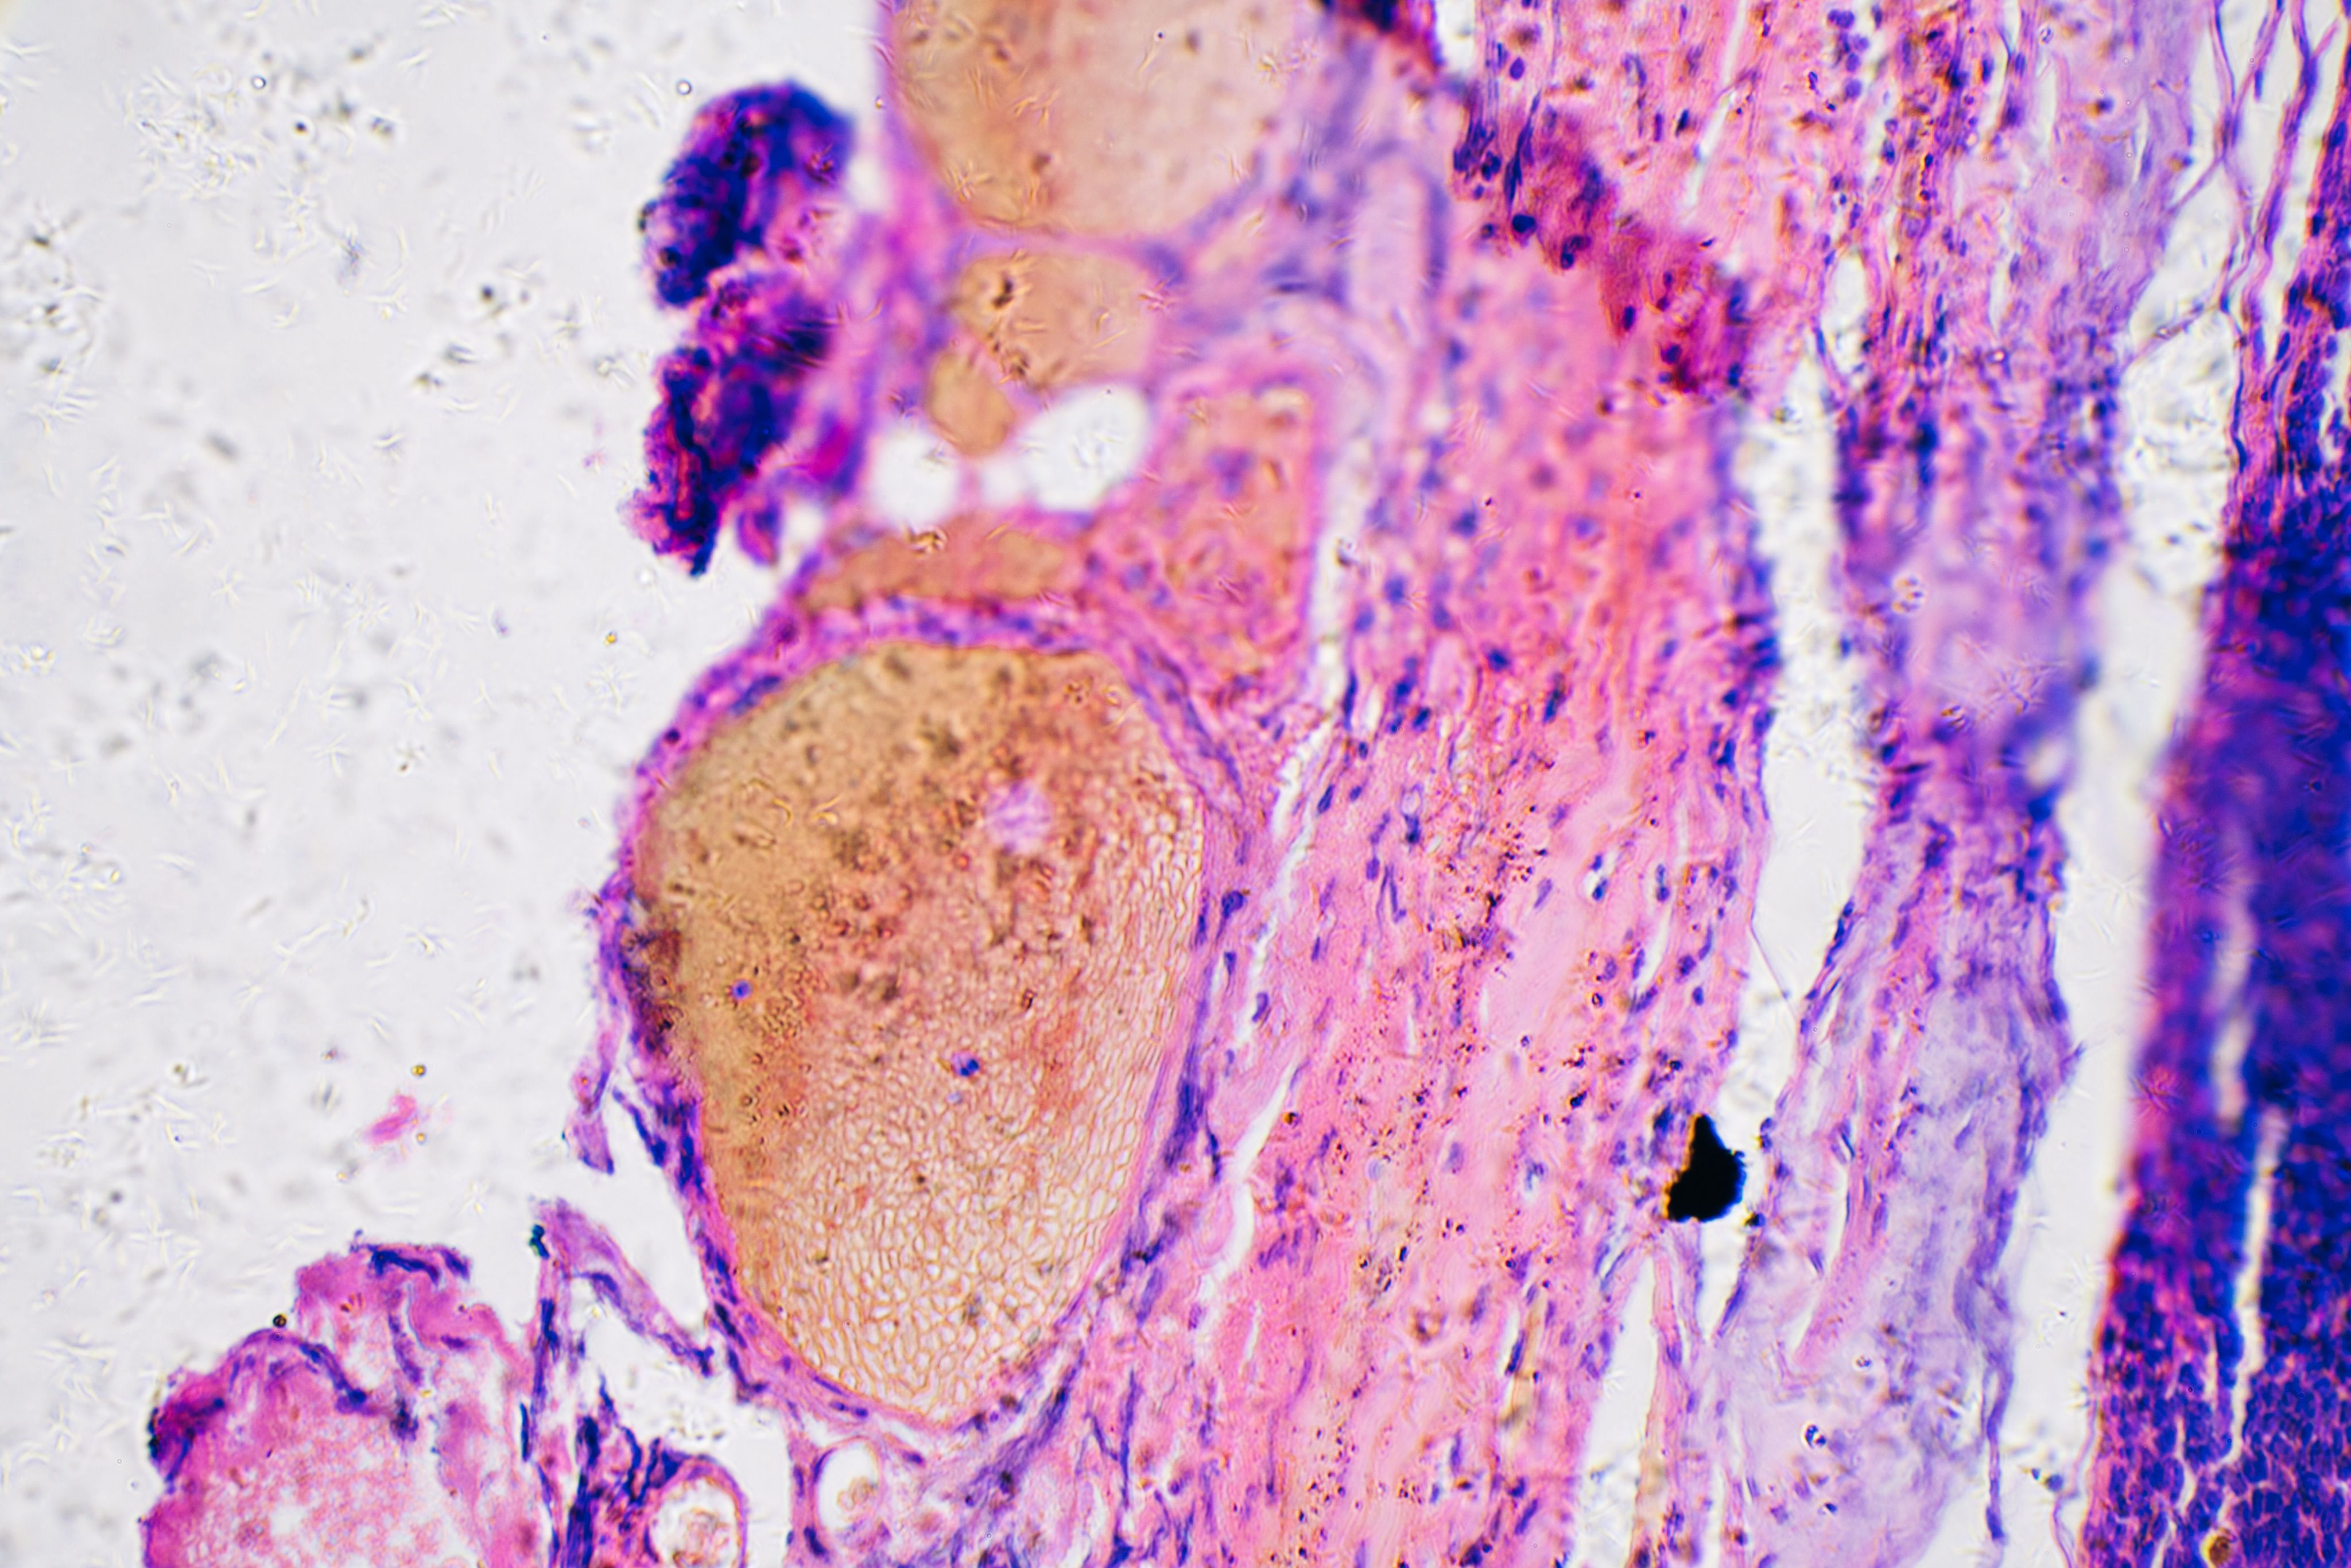

Microscope image showing the cells in different layers of skin. It appears pink, blue, purple and red.

A microscope image showing layers of healthy skin. Jose Luis Calvo/Shutterstock.com

But our skin isn’t all one thing. It’s made up of different cells working together. Depending on the type of cells they start in, skin cancers have different names and behave in different ways.

The biggest difference is the one that separates melanoma skin cancers, which start in the cells that give skin its colour (melanocytes), from non-melanoma skin cancers, which usually start in the cells that make skin an effective barrier (keratinocytes).